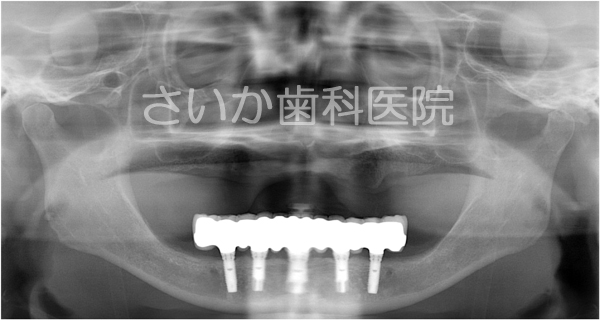

総入れ歯の患者様です。下の入れ歯が安定せず,食事に不自由であるため,インプラント治療を選択しました。

このケースは事前に撮影したCT画像をコンピュータ解析し,歯ぐきを切らずにインプラントを埋め込む方法です(当院の患者様ですが,当院で初めてのケースでしたので奈良県五條市にある中谷歯科医院の堀内克啓先生にご協力いただきました)。

歯ぐきを切らないでインプラントを入れ,その日のうちに「仮の歯」を入れました。写真は手術翌日ですが,歯ぐきの腫れはほとんどありません。食事も柔らかい物であれば手術直後から普通に出来ました。

半年経過してから最終的な歯を作りました。処置終了してまだ3年ほどですが順調に経過しています。